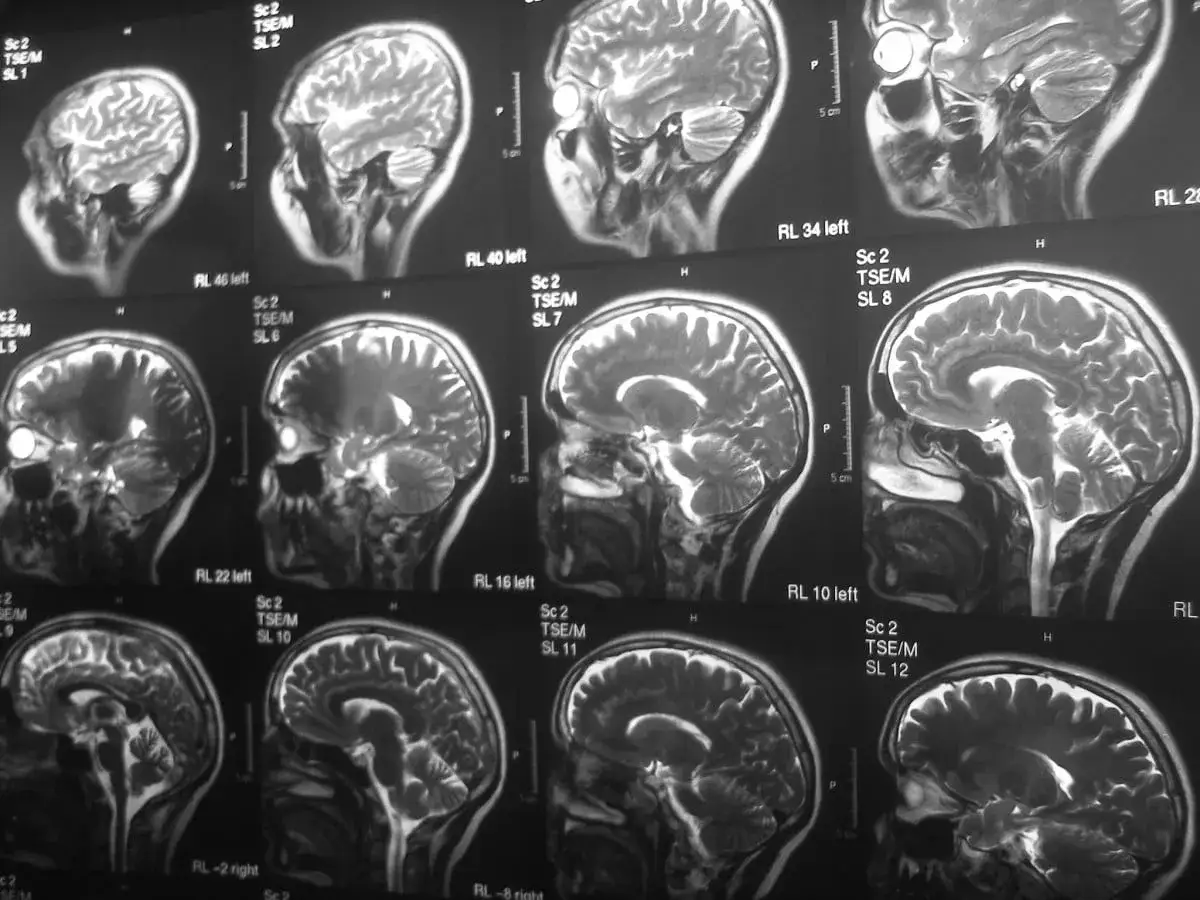

Rezonans magnetyczny (MRI) głowy nie jest narzędziem do bezpośredniego diagnozowania schizofrenii. Schizofrenia nie jest chorobą, którą można "zobaczyć" na obrazie MRI w taki sam sposób, jak na przykład guz mózgu czy ogniskę zapalne. Badanie to pokazuje nam strukturę anatomiczną mózgu i pozwala wykryć ewentualne zmiany patologiczne, ale nie jest w stanie zdiagnozować samej choroby psychicznej, jaką jest schizofrenia.

Główną rolą rezonansu magnetycznego w procesie diagnostycznym, gdy podejrzewamy psychozę, jest tak zwana diagnostyka różnicowa. Jest to proces, w którym lekarz stara się wykluczyć inne, organiczne przyczyny objawów, które mogą przypominać schizofrenię. Obraz MRI pozwala ocenić, czy objawy nie są spowodowane przez problemy neurologiczne lub inne schorzenia somatyczne, które mogłyby wpływać na funkcjonowanie mózgu.

Podczas badania MRI lekarz analizuje budowę mózgu, szukając nieprawidłowości takich jak guzy, zmiany naczyniowe, stany zapalne czy uszkodzenia wynikające z urazów. Jeśli takie zmiany zostaną wykryte, mogą one stanowić przyczynę objawów psychotycznych i wymagać innego leczenia niż schizofrenia. Jeśli jednak obraz mózgu jest prawidłowy, a objawy sugerują schizofrenię, lekarz może z większą pewnością postawić takie rozpoznanie, bazując na innych metodach diagnostycznych.

Badania naukowe, wykorzystujące zaawansowane techniki neuroobrazowania, takie jak rezonans magnetyczny, rzeczywiście wskazują na istnienie pewnych subtelnych różnic w budowie i funkcjonowaniu mózgu u osób chorujących na schizofrenię w porównaniu do osób zdrowych. Obserwacje te są niezwykle cenne dla naukowców próbujących zrozumieć podłoże choroby, jednak kluczowe jest podkreślenie, że nie są one podstawą do postawienia jednoznacznej diagnozy u konkretnego pacjenta.

W badaniach strukturalnego MRI często obserwuje się pewne zmiany anatomiczne. Należą do nich między innymi: zmniejszenie objętości istoty szarej, która zawiera ciała komórek nerwowych, szczególnie w obszarach takich jak płaty skroniowe i czołowe mózgu. Zdarza się również, że stwierdza się poszerzenie komór bocznych mózgu, czyli przestrzeni wypełnionych płynem mózgowo-rdzeniowym. Te zmiany są jednak statystyczne nie występują u wszystkich osób ze schizofrenią i mogą być obecne również u osób zdrowych, choć rzadziej.

Bardziej zaawansowane techniki, takie jak funkcjonalny rezonans magnetyczny (fMRI), pozwalają na badanie aktywności mózgu podczas wykonywania określonych zadań. U osób ze schizofrenią badania te często pokazują nieprawidłowości w funkcjonowaniu sieci neuronalnych, czyli sposobie, w jaki różne obszary mózgu komunikują się ze sobą. Może to wpływać na procesy poznawcze, emocjonalne i behawioralne.

Niemniej jednak, te obserwowane różnice są zazwyczaj zbyt subtelne i niespecyficzne, aby można było na ich podstawie jednoznacznie zdiagnozować schizofrenię u pojedynczej osoby. Wiele z tych zmian może być również związanych z innymi czynnikami, takimi jak przyjmowane leki, styl życia czy inne współistniejące schorzenia. Dlatego też, według danych Podyplomie.pl, neuroobrazowanie w schizofrenii jest głównie narzędziem badawczym, a nie standardem diagnostycznym.